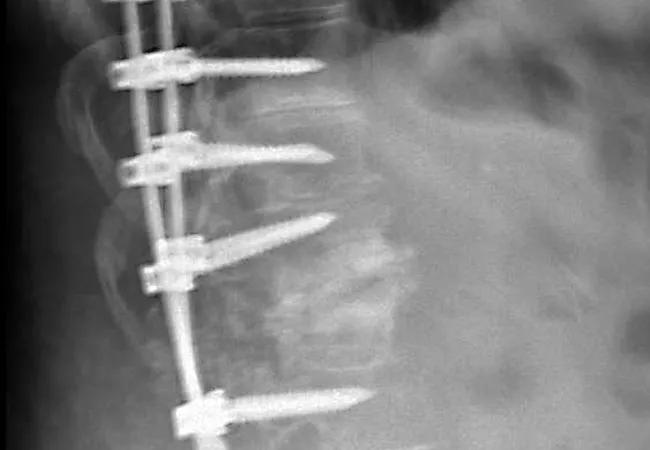

Intraoperative multimodal (IOM) monitoring, which provides real-time feedback on spinal cord integrity, did not lead to better outcomes in patients undergoing a pedicle subtraction osteotomy (PSO) of the lumbar spine during a decade’s experience involving 101 patients at Cleveland Clinic. So concludes a retrospective study presented at the American Association of Neurological Surgeons (AANS) 2019 annual scientific meeting this week.

IOM monitoring — which most commonly uses motor and somatosensory evoked potentials and spontaneous (free-running) electromyography — has largely become standard practice for PSOs of the thoracic spine. It is used in an effort to minimize accidental neurological injury to the spinal cord, nerve roots and associated structures. Iatrogenic injury from surgery to correct a spine deformity can range from minor sensory disturbances to complete paralysis.

But while benefits of IOM monitoring for PSOs on the thoracic spine have been documented in other studies, its usefulness is less certain for PSOs of the lumbar spine, where the spinal cord typically extends only to the level of the first or second lumbar vertebra. Accordingly, guidelines for its use in this setting have not been established. As a result, whether IOM monitoring is used during a PSO of the lumbar spine is largely a matter of surgeon preference.